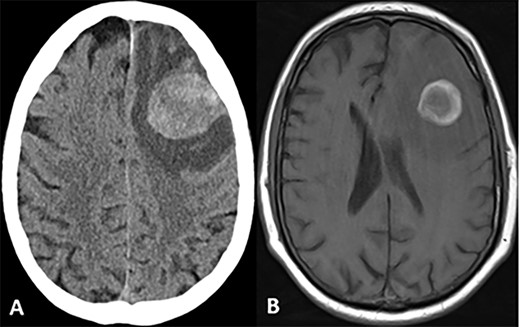

CASE

CT and MRI scans of the head indicating a large hemorrhagic enhancing lesion in the left frontal lobe with surrounding edema causing a rightward midline shift.